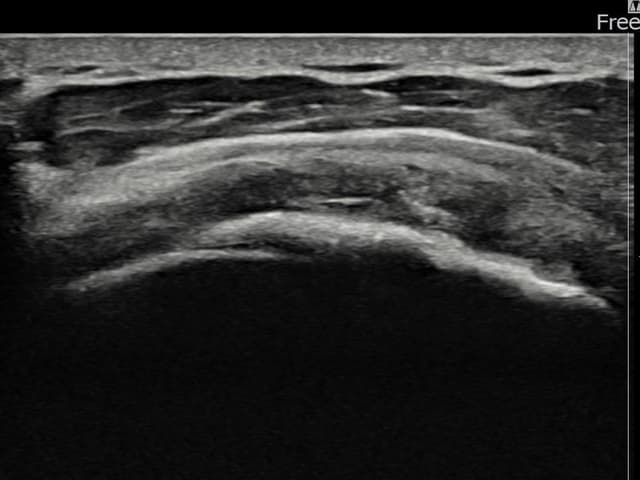

[経過期間: 23.07.18~23.09.14]

[縫縮術] 超音波検査にて左 棘上筋腱 광범위 部分断裂(15mm × 6mm (腱厚の約70%欠損))を確認。縫縮術施行後、腱の連続性が回復し、日常生活に復帰されました。